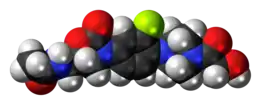

| 3D model (JSmol) | |

| Formula | C18H23FN4O5 |

| Molar mass | 394.40 g·mol−1 |

Eperezolid is an oxazolidinone antibiotic.